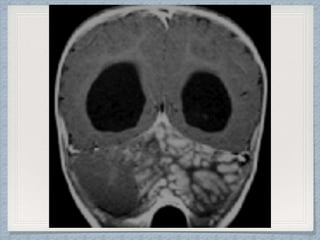

Radiological Findings Of

Retinoblastoma

USG

CT

MRI